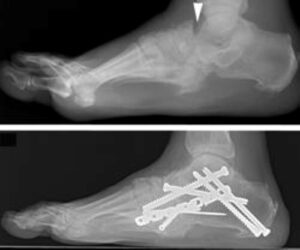

- X-rays: X-rays are a crucial diagnostic tool for Charcot foot. In the early stages, X-rays may appear normal. However, as the condition advances, signs such as fractures, bone fragments, and joint destruction become evident. Over time, more severe deformities, dislocations, and new bone formations may develop, indicating progressive Charcot arthropathy.

The patient shown in the X-ray had noticed swelling of the foot for approximately 3 weeks without any known injury. The X-ray shows several fractures (arrowheads) and a dislocation of the first metatarsal (arrow). Such a severe injury in patients without diabetes would be seen only after a high-energy trauma.